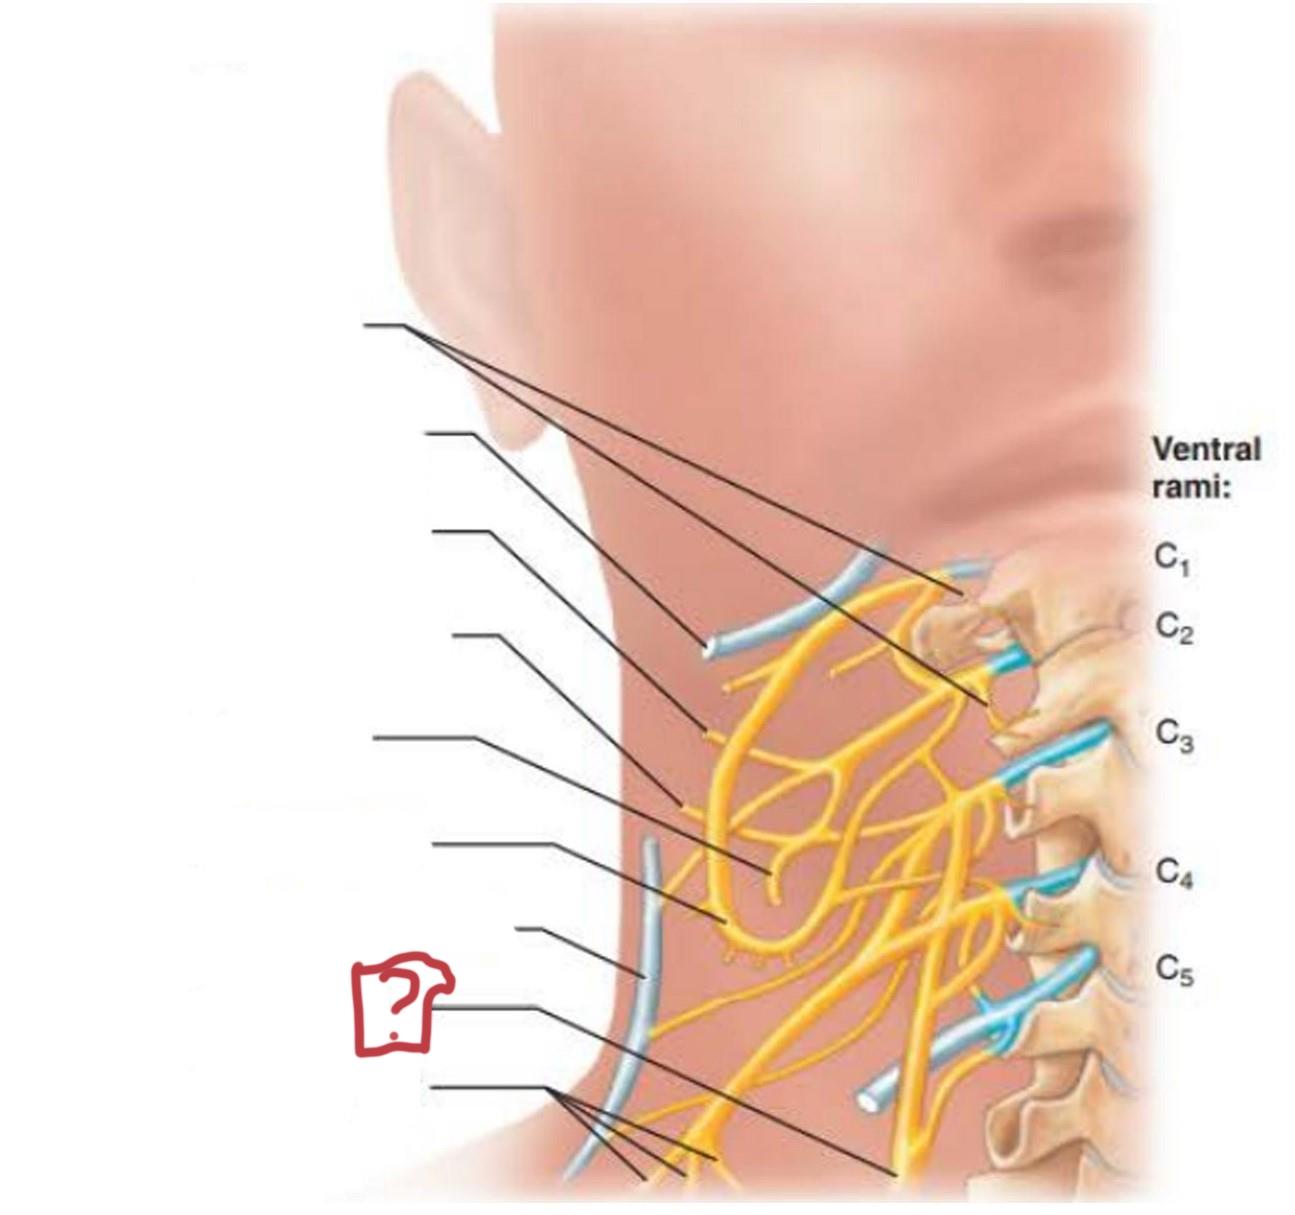

cervical plexus

C1-C4

segmental branches

hypoglossal nerve (12)

lesser occipital nerve

greater auricular nerve

transverse cervical nerve

ansa cervicalis

accessory nerve (11)

phrenic nerve

supraclavicular nerves